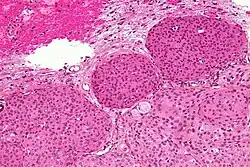

Micrograph of a meningioma with brain invasion (WHO Grade II). The tumour (bottom/right of image) has the typical "pushing border" invasion into the cerebral cortex (top/left of image), HPS stain.

Meningiomas arise from arachnoidal cap cells,[17] most of which are near the vicinity of the venous sinuses, and this is the site of greatest prevalence for meningioma formation. Some subtypes may arise from the pial cap cells that migrate during the development together with blood vessels into the brain parenchyma.[18] They most frequently are attached to the dura over the superior parasagittal surface of frontal and parietal lobes, along the sphenoid ridge, in the olfactory grooves, the Sylvian region, superior cerebellum along the falx cerebri, cerebellopontine angle, and the spinal cord. The tumor is usually gray, well-circumscribed, and takes on the form of the space it occupies. They usually are dome-shaped, with the base lying on the dura.

Histologically, meningioma cells are relatively uniform, with a tendency to encircle one another, forming whorls and psammoma bodies (laminated calcific concretions).[19] As such, they also have a tendency to calcify and are highly vascularized.